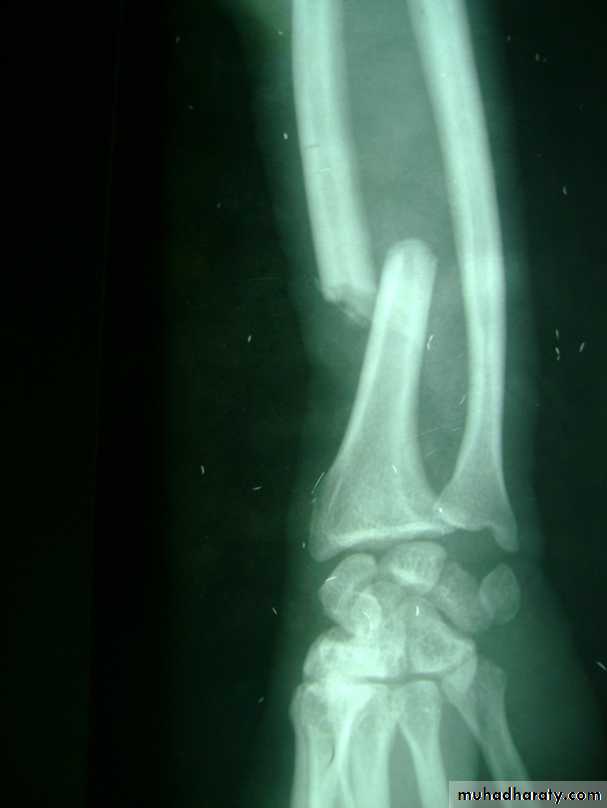

Slide 3A 30 Years old man presented with pain and deformity in forearm following fall on ground1- What is the diagnosis?2- what is the best method of treatment?